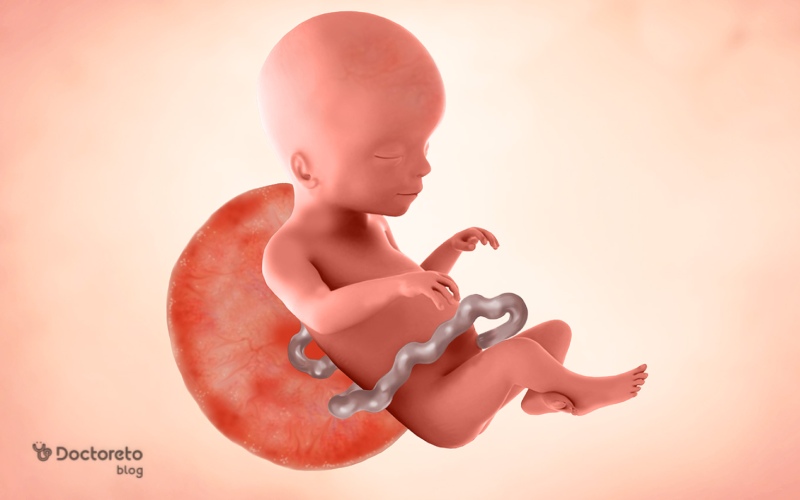

در هفته ۲۲ بارداری شما وارد نیمه دوم بارداری شدهاید و جنینتان حالا شبیه یک نوزاد کوچک است، با اندازهای حدود ۲۸ سانتیمتر و وزنی نزدیک به ۵۰۰ گرم. ریهها، مغز و حواس جنین در حال تکامل سریع هستند و ممکن است حرکات او را بیشتر احساس کنید. برای مادر، علائم مانند تهوع اغلب کاهش یافته اما ممکن است با بزرگشدن شکم، دردهای خفیف یا تغییرات پوستی روبرو شوید. این هفته معمولا با انرژی بیشتر همراه است اما مراقبت از علائم احتمالی زایمان زودرس ضروری است. در ادامه مقاله، جزئیات رشد جنین، علائم رایج، آزمایشها و نکات مراقبتی را بررسی میکنیم تا بارداریتان را با اطمینان بیشتری پیش ببرید.

در هفته 22 بارداری جنین حدود ۲۸ تا ۳۰ (از سر تا پا) میشود. وزن جنین در این هفته تقریبا ۴۰۰ تا ۵۰۰ گرم است. تغییرات زیر در این هفته در جنین ایجاد میشوند:

در هفته بیستم و دوم بارداری جنین چه شکلی است؟

در هفته بیست و دوم بارداری جنین به رشد ادامه میدهد و حدود ۳۰ سانتیمتر است. پلکها بسته هستند اما جنین میتواند چشمهای خود را حرکت دهد. موهای بسیار ظریف بهعنوان ابرو رشد کردهاند. جنین به صداهای خارجی واکنش نشان میدهد. بهعنوان مثال ممکن است در پاسخ به یک صدا دست و پاهای خود را به هم نزدیک کند.